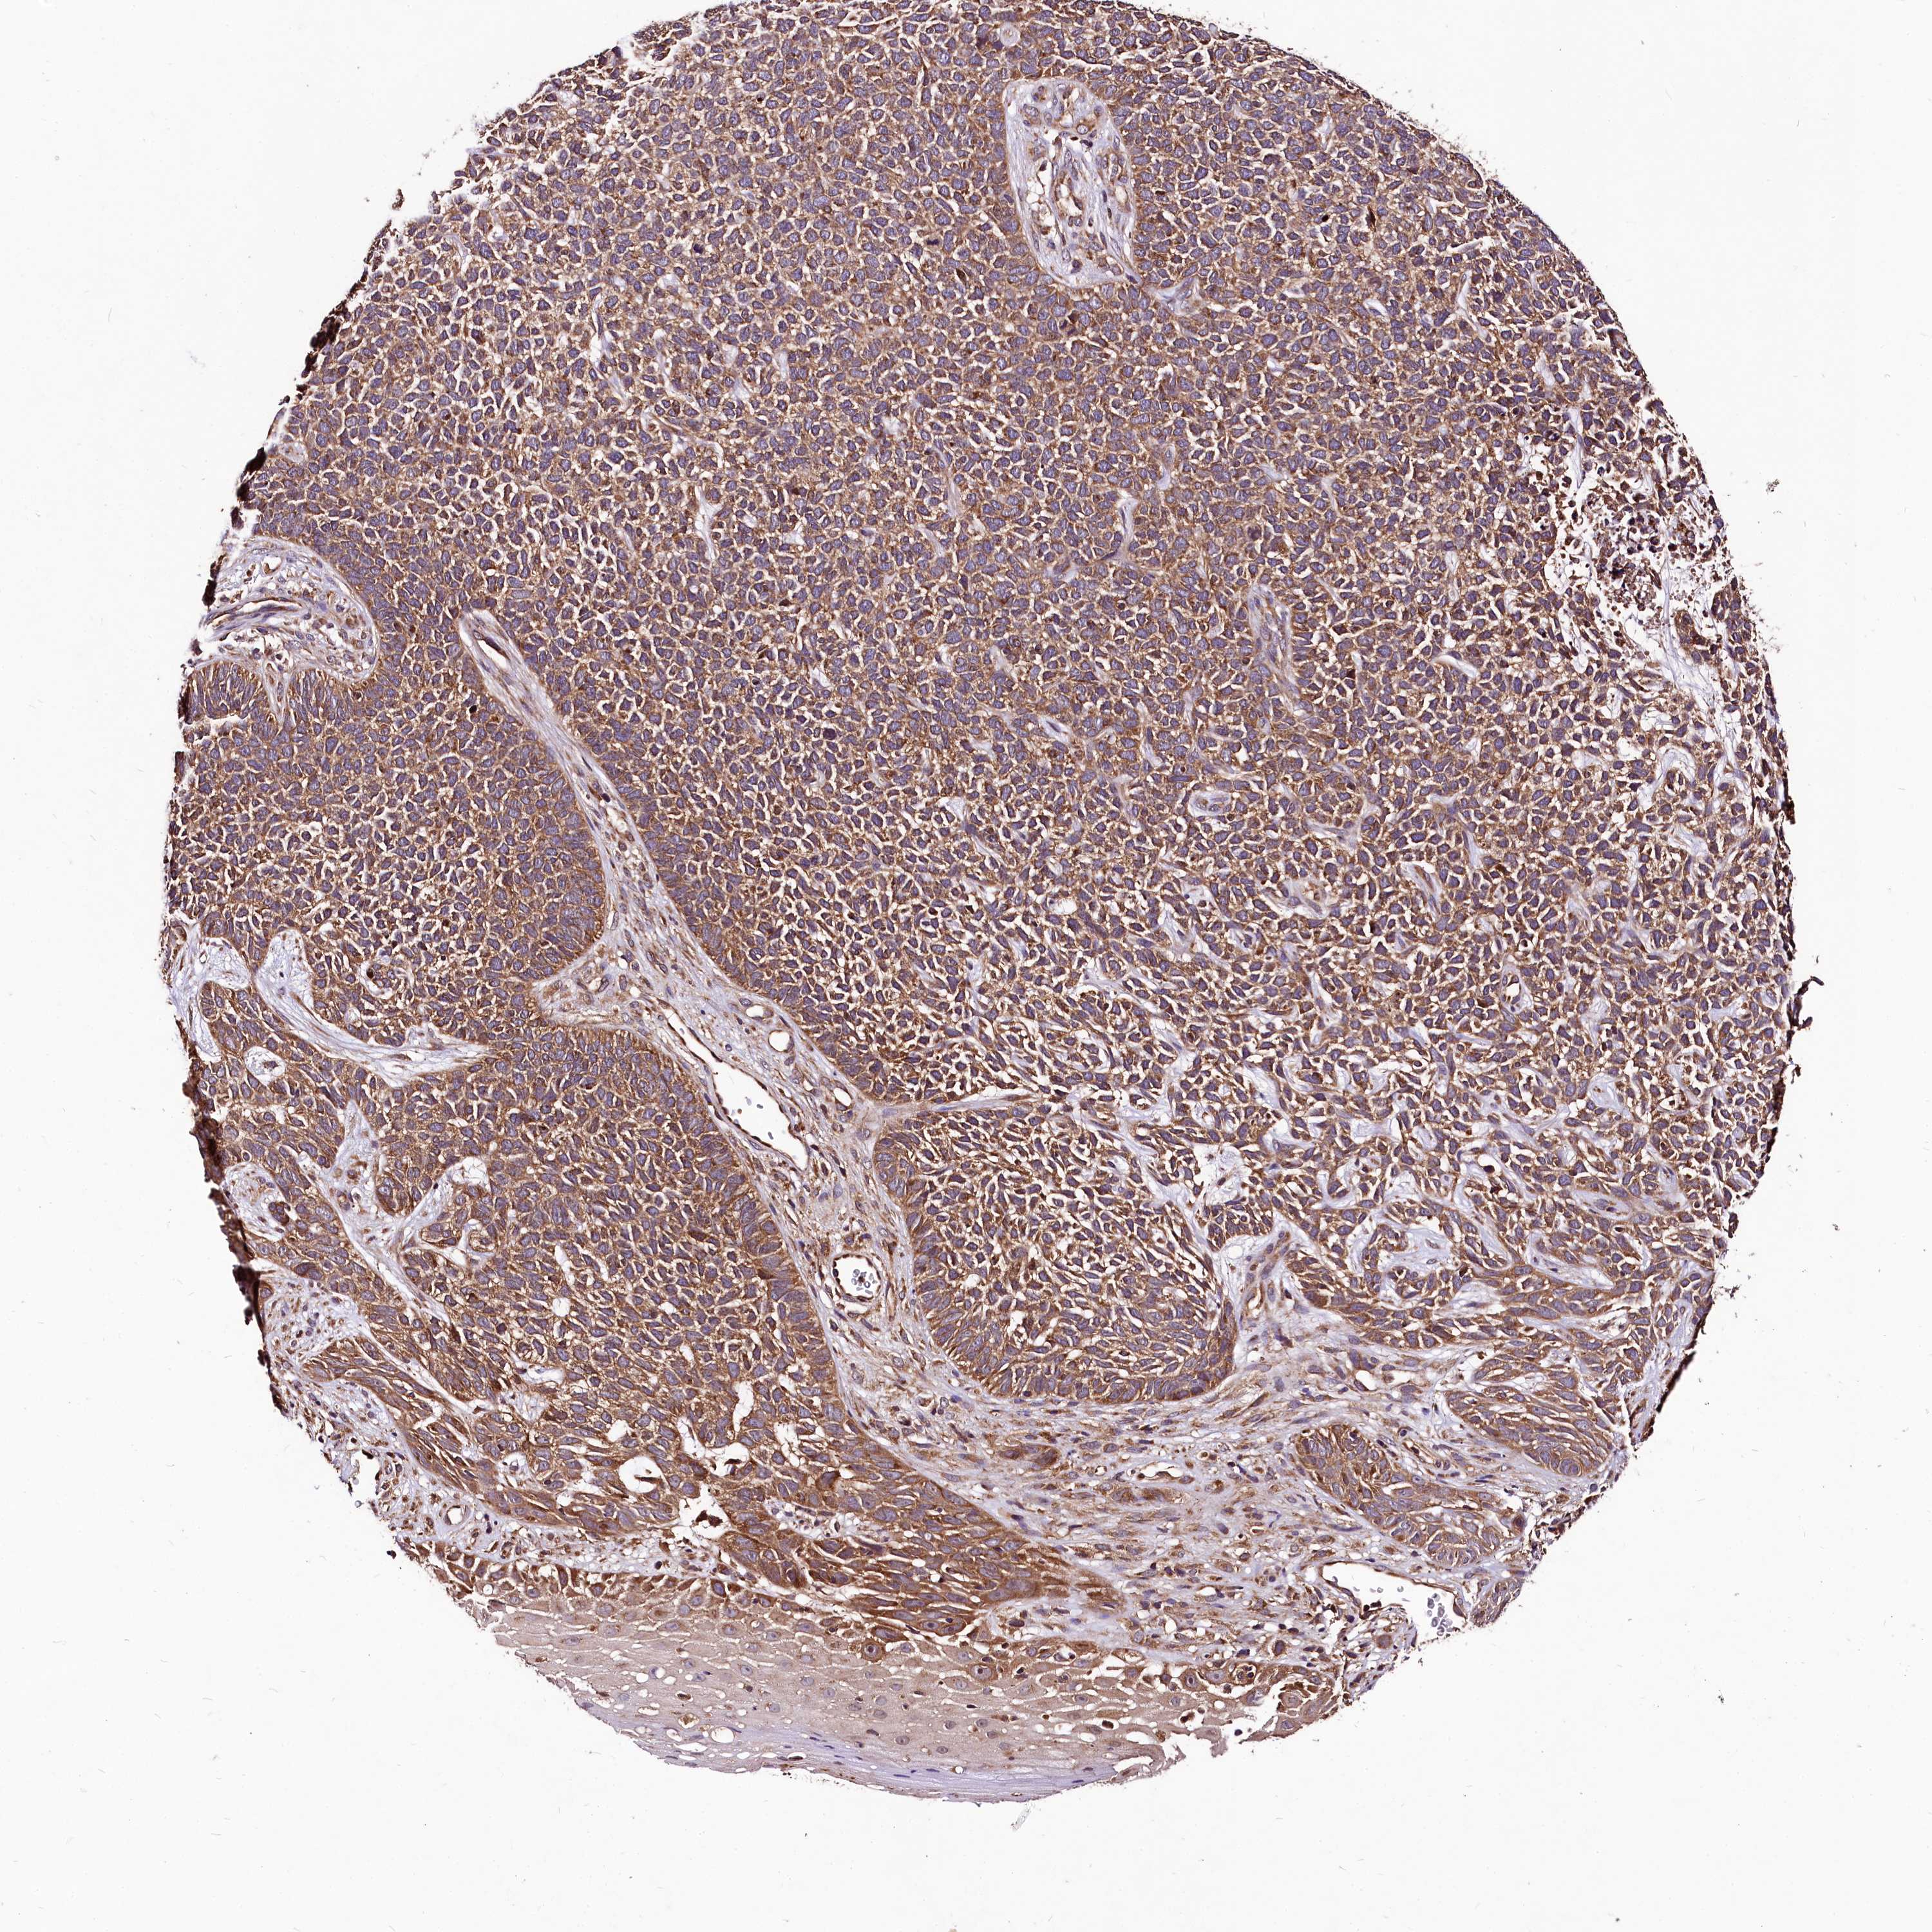

SKIN CANCER - Protein expressioni

A mouse-over function shows sample information and annotation data. Click on an image to view it in a full screen mode. Samples can be filtered based on level of antibody staining by selecting one or several of the following categories: high, medium, low and not detected. The assay and annotation is described here.

Each image is clickable and will lead to virtual microscopy that enables deeper exploration of all samples and also displays staining intensity scores, fraction scores and subcellular localization as well as patient and tissue information for each sample.

Antibody HPA021403

Antibody HPA021844

Antibody CAB037304

Staining

High

Medium

Low

Not detected

Intensity

Strong

Moderate

Weak

Negative

Quantity

>75%

75%-25%

<25%

None

Location

Nuclear

Cytoplasmic/membranous

Cytoplasmic/membranous,nuclear

Basal cell carcinoma

Squamous cell carcinoma, NOS

Squamous cell carcinoma, metastatic, NOS

Squamous cell carcinoma in situ, NOS

Adnexal tumor, benign